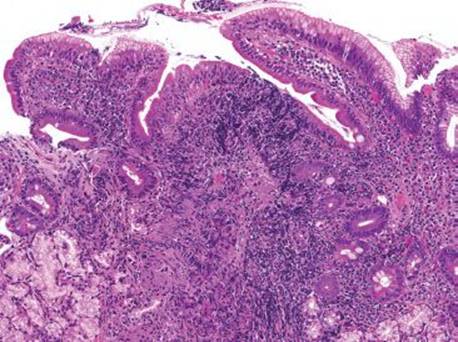

This case was received as “prominent ampulla, concerning for malignancy” (Fig. 3.313). The initial sections show duodenal mucosa with acute and chronic inflammation, gastric foveolar metaplasia, and marked reactive epithelial change (Fig. 3.313). Although these histologic features can account for a nodular clinical impression, deeper sections were pursued based on the clinical suspicion for malignancy. The first set of deeper sections were similarly concerning, but definitive malignancy was not seen. Deeper sections were repeated. And repeated. And repeated. In this case, the tissue block was exhausted and on the 38th level (!!!), clear lymphovascular invasion and infiltrating adenocarcinoma were seen (Figs. 3.314 and 3.315). When the histology does not fit the clinical scenario, consider deeper sections. When the deeper sections are not conclusive, consider repeat deeper sections or recommend rebiopsy (in this case, the patient was too unstable for a subsequent biopsy).

Figure 3.314 Infiltrating poorly-differentiated adenocarcinoma and lymphovascular space invasion. Deeper sections were performed until the block was exhausted. This photomicrograph represents the 38th (and final) section, which shows desmoplasia, infiltrating adenocarcinoma (arrowheads), and lymphovascular space invasion (asterisk). These deeper sections show an entirely different biopsy compared to the initial sections and were sufficient for chemotherapy initiation.

Figure 3.315 Sneaky adenocarcinoma involving the duodenal mucosa. Under oil immersion, note the nuclear irregularities, abundant pink cytoplasm, and cytoplasmic mucin droplet (arrowhead) characteristic of pancreatobiliary adenocarcinoma. Unfortunately, sometimes 38 levels are required for the ultimate diagnosis and sometimes only a few malignant cells are present! When the clinical scenario and the histology are not aligned, deeper sections (and deeper sections and deeper sections and deeper sections) are often required.